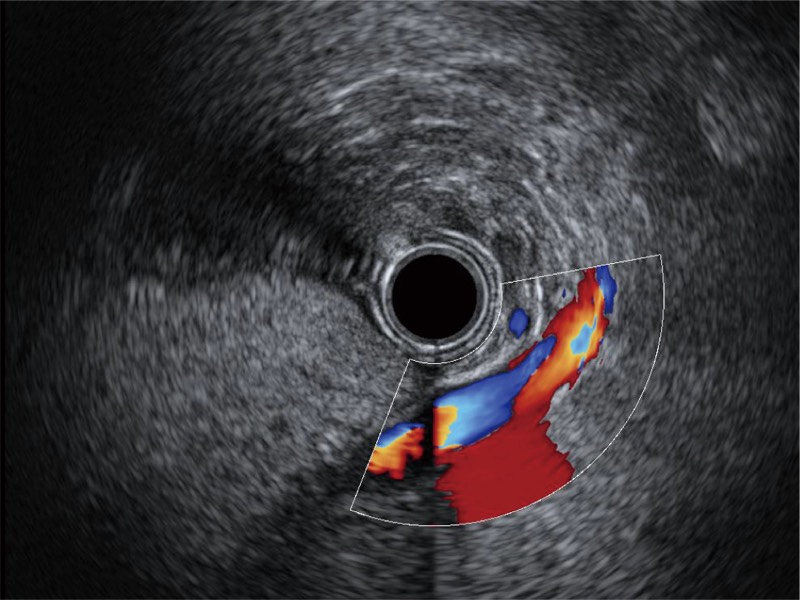

• 清晰显示胆总管及周围血管分布

• 非线性融合造影

融合谐波技术

动态声压控制技术